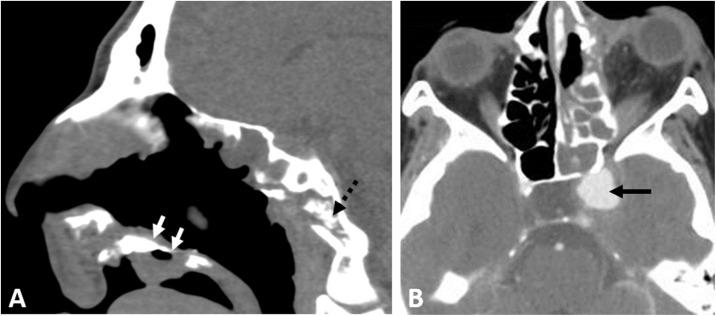

This is a case series presenting the radiologic features and clinical presentation of acute invasive fungal rhino-orbital-cerebral sinusitis (AIFS) in eight hospitalized patients with confirmed COVID-19 infection.

Our patient cohort presented with symptoms of the invasive fungal disease within 12-35 days from their initial presentation with COVID-19 infection. The cross-sectional imaging features of AIFS associated with COVID-19 infection do not differ from those reported in the literature for AIFS associated with other risk factors, yet our patients had features of aggressive late-stage forms with high morbidity and mortality rate.